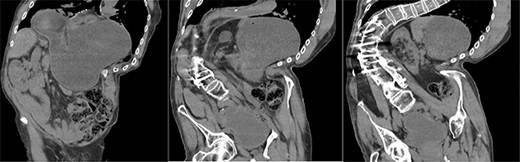

A 67-year-old man presented to the emergency department with sudden onset epigastric abdominal pain and vomiting, on a background of a known hiatus hernia awaiting surgical management. The patient continued passing flatus but was not able to tolerate any per oral fluid intake, vomiting any intake that was attempted. Medical history was relevant for severe KS, spina bifida, reflux, recurrent urinary tract infection, and an anterior approach spinal fusion surgery. Examination was significant for severe KS, with a soft and non-tender abdominal examination. Biochemically, the patient had a very mildly raised white cell count of 12.6 † 109/l. A CT of the abdomen and pelvis was obtained that identified the progression of a known hiatus hernia in comparison with an earlier CT, containing the distal portion of the stomach. The CT showed a distended and fluid filled oesophagus and stomach, along with fat stranding around the distal stomach, concerning for obstruction and possible strangulation of the moderate hiatus hernia, along with the known severe KS (see Figs 1 and 2). A nasogastric tube was placed to decompress the stomach (see Fig. 3). Following discussion with the patient regarding their current presentation and risks of operative management, laparoscopic hiatus hernia repair and fundoplication was undertaken, which was uncomplicated, although the dissection was difficult secondary to the severe scoliosis. Intra-operatively, it was noted that the hernial sac contained a grossly dilated stomach, with all hernial contents assessed as being viable, with nil signs of ischaemia. The peritoneal sac was not resected and left in situ, with a four-stitch horizontal posterior cruroplasty undertaken, along with a 180-degree anterior fundoplication. There was concern that recovery may be complicated by respiratory failure due to the severe KS; however, the patient had no respiratory compromise, begun passing flatus, opened his bowels, and tolerated a puree diet in the days following the operation. At post-operative clinic review 4 months following the hiatus hernia repair, the patient was well, described nil issues, and was tolerating a full diet.

Chest X-ray showing nasogastric decompression of hiatus hernia, along with severe kyphoscoliosis.